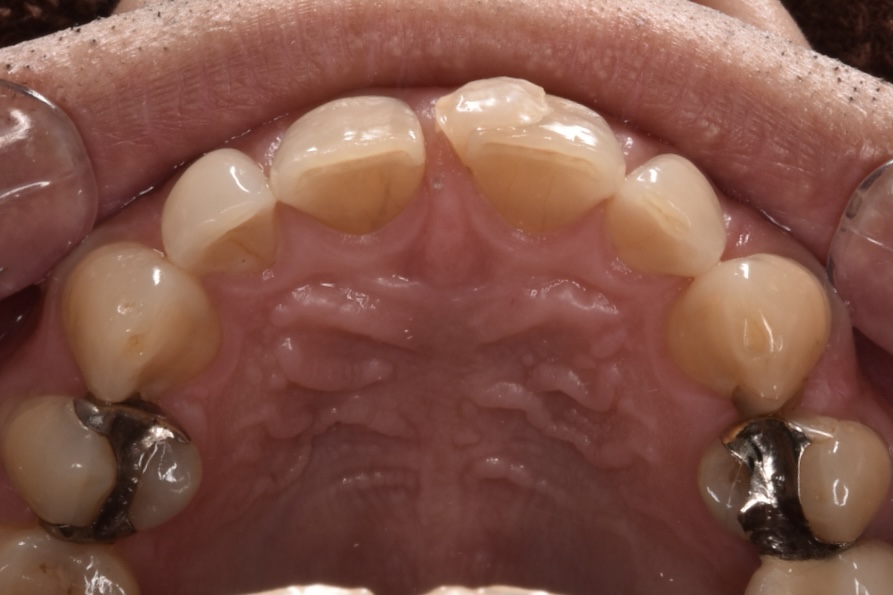

施術前

当院でタイレクトボンディング2歯のやりかえをご希望されて、2本でご契約してくださいました。他院のレジンは前日に取れたそうです。